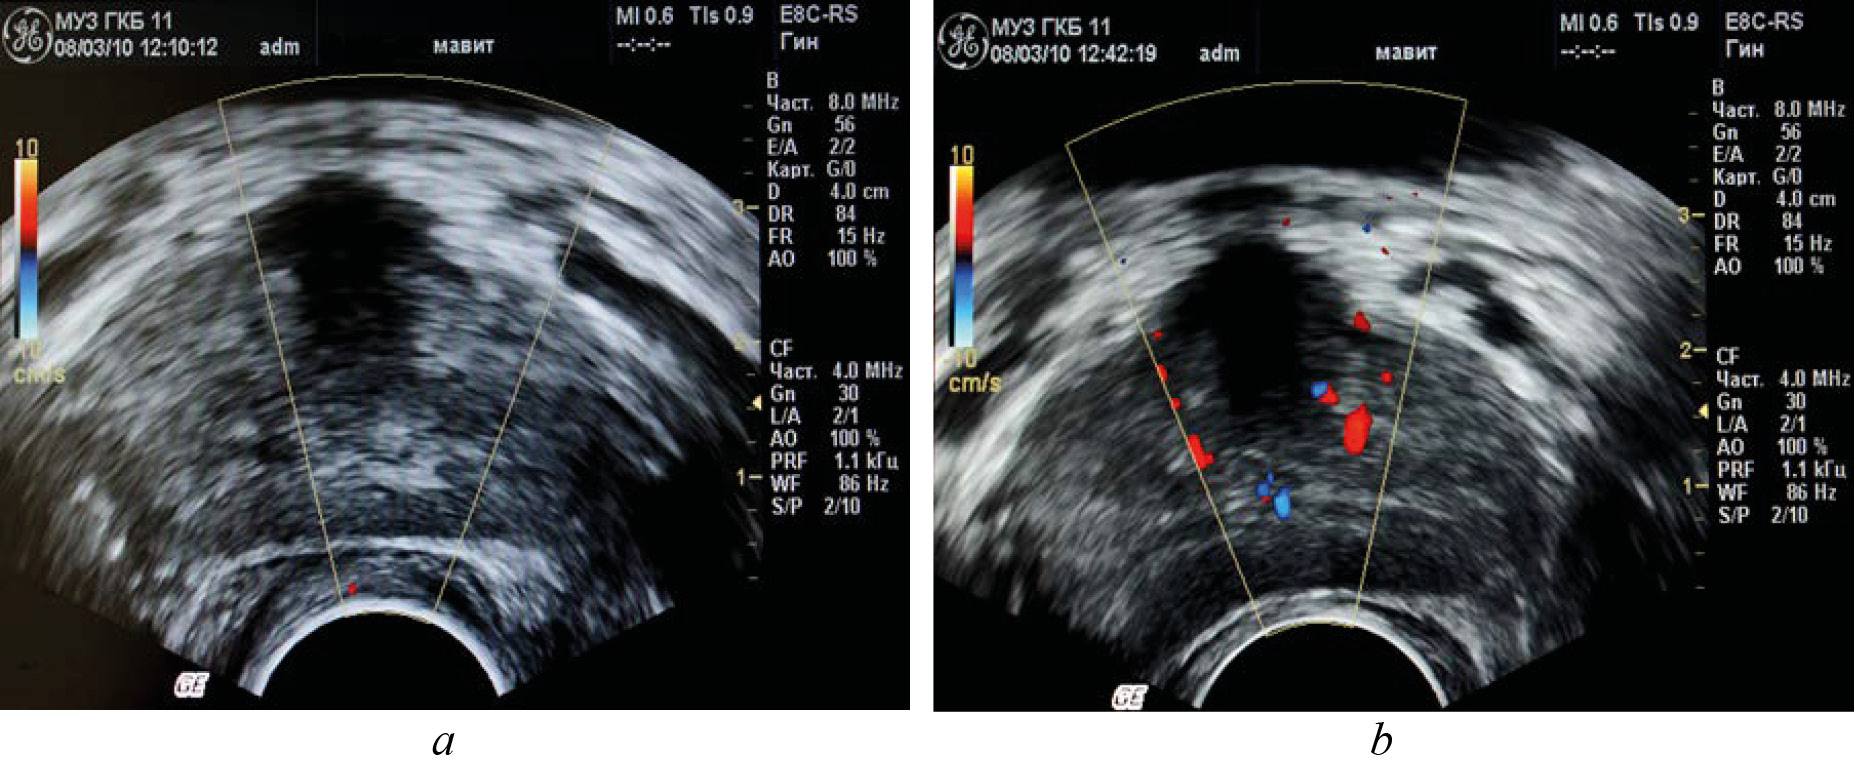

To evaluate prostatic blood flow after a local physiotherapy treatment using the MAVIT device, 10 patients had transrectal (color Doppler mapping) ultrasound of the prostate before and after the treatment, which showed improved microcirculation in the prostate tissue. MAVIT therapy resulted in a pronounced reaction of improved circulation throughout the vascular basin (see Fig. 3). The average linear peak velocity in the studied subgroup increased by 1.1 times and the resistance index decreased by 1.2 times compared to the baseline. The average vascular density increased by more than 2.5 times.

Fig. 3. Dopplerogram of the prostate before (a) and after (b) the session of physiotherapy on the device MAVIT.